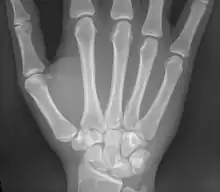

Os humain de la main